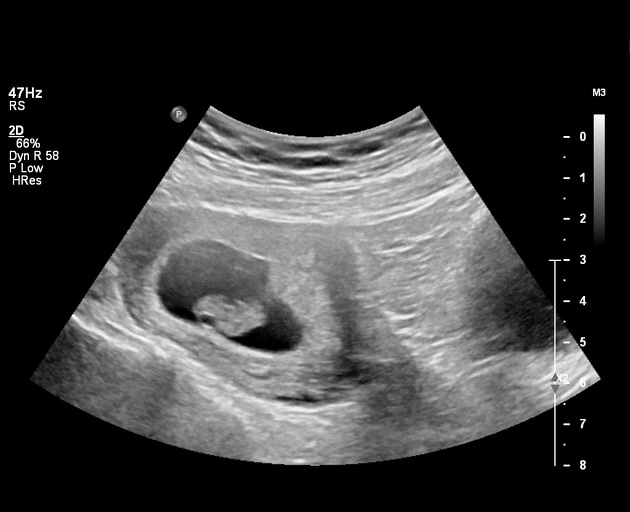

Gambar USG dengan tampilan gelombang detak jantung (M-Mode) | Sumber: Emory School of Medicine

Pada trimester pertama, tanda janin sehat terlihat dari perkembangan organ dan struktur tubuh yang sesuai usia kehamilan, gerakan janin yang mulai terjadi, serta detak jantung yang sudah dapat dideteksi secara ultrasonografi pada minggu ke-12.

Perkembangan ini menjadi patokan penting dalam memastikan janin tumbuh dengan baik di masa awal

1. Detak Jantung Janin Terdengar

Detak jantung janin terdengar adalah momen yang sangat mengharukan dan paling melegakan bagi setiap calon orang tua.

Saat dokter melakukan USG, mendengarkan detak jantung janin untuk pertama kalinya adalah konfirmasi nyata bahwa kehidupan baru telah dimulai.

Umumnya, detak jantung janin baru bisa terdeteksi melalui USG transvaginal pada usia kehamilan sekitar 6–7 minggu

2. Frekuensi Detak Jantung Normal

Setelah terdeteksi, hal berikutnya yang diperhatikan adalah ritmenya. Janin yang sehat dan berkembang baik di awal kehamilan memiliki denyut jantung cepat, biasanya berkisar antara 110 hingga 160 detak per menit (bpm).

Detak jantung yang stabil dan berada dalam batas normal ini menjadi ciri-ciri janin kuat susah keguguran, sehingga menunjukkan sistem vitalnya berfungsi optimal.